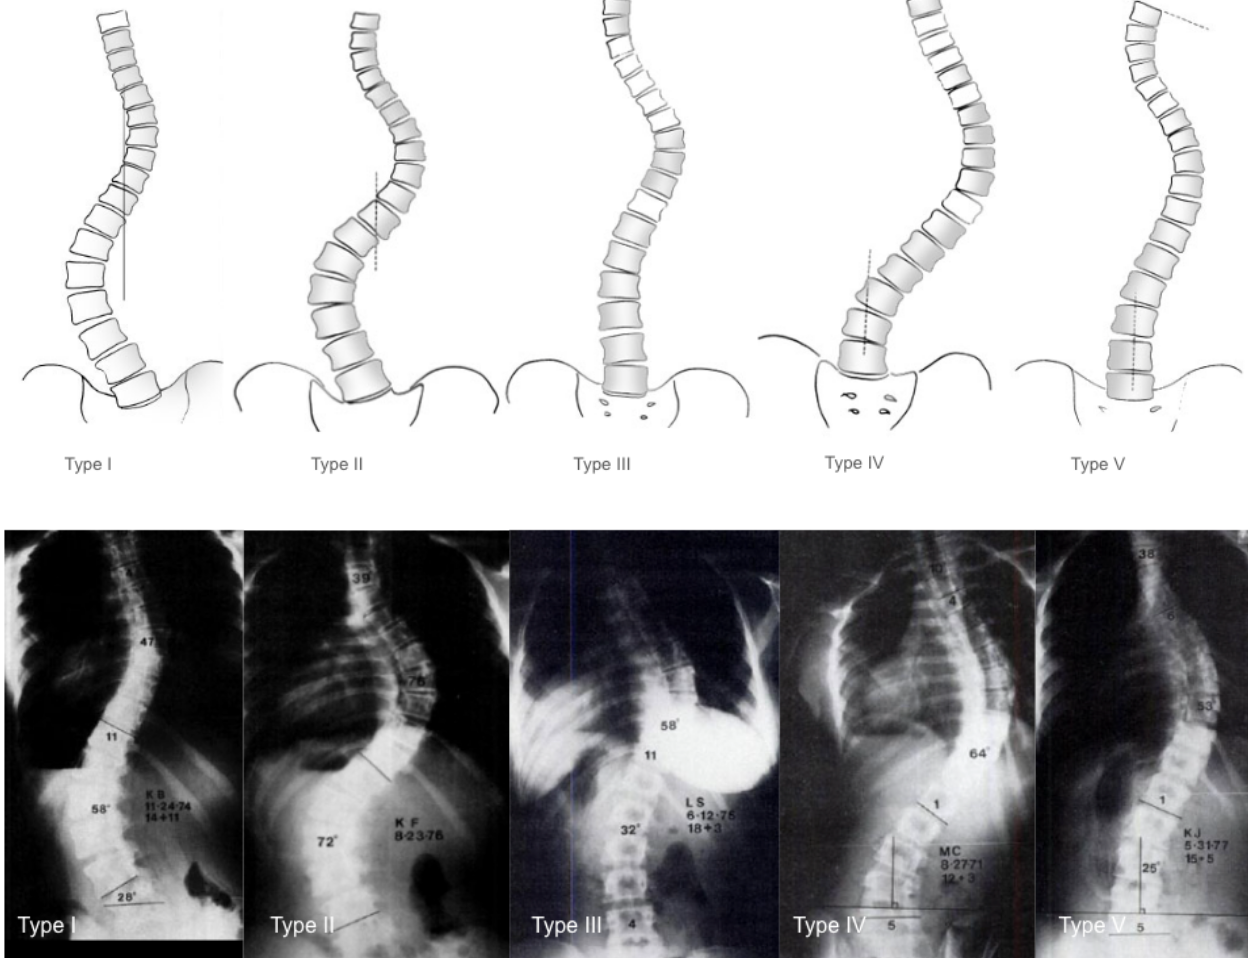

The system describes five coronal curve types (Types I–V), focusing exclusively on coronal alignment (based on the central sacral vertical line) without considering sagittal profile or three-dimensional deformity.

• Type I: S-shaped (double curve) with both lumbar and thoracic curves crossing midline; lumbar curve generally larger and stiffer than thoracic curve; FI is generally negative (thoracic curve ≥ lumbar curve standing and more flexible with side-bending)

• Type II: S-shaped (double curve) with both lumbar and thoracic curves crossing midline; thoracic curve generally larger and stiffer than lumbar curve; FI generally positive

• Type III: Prominent thoracic curve with minimal lumbar compensation (does not cross midline); thoracic ‘overhang’

• Type IV: Long thoracic curve where L5 is positioned over sacrum but L4 tilts into thoracic curve

• Type V: Double thoracic curve with T1 tilting into apex of upper curve; upper curve appears structural on side-bending